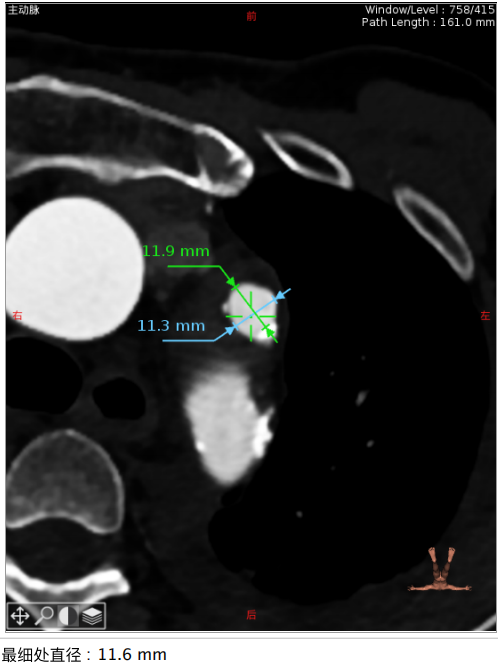

CT分析结果:

图示:瓣环、左室流出道、主动脉窦、升主动脉、窦管结合及瓣上结构部大小。